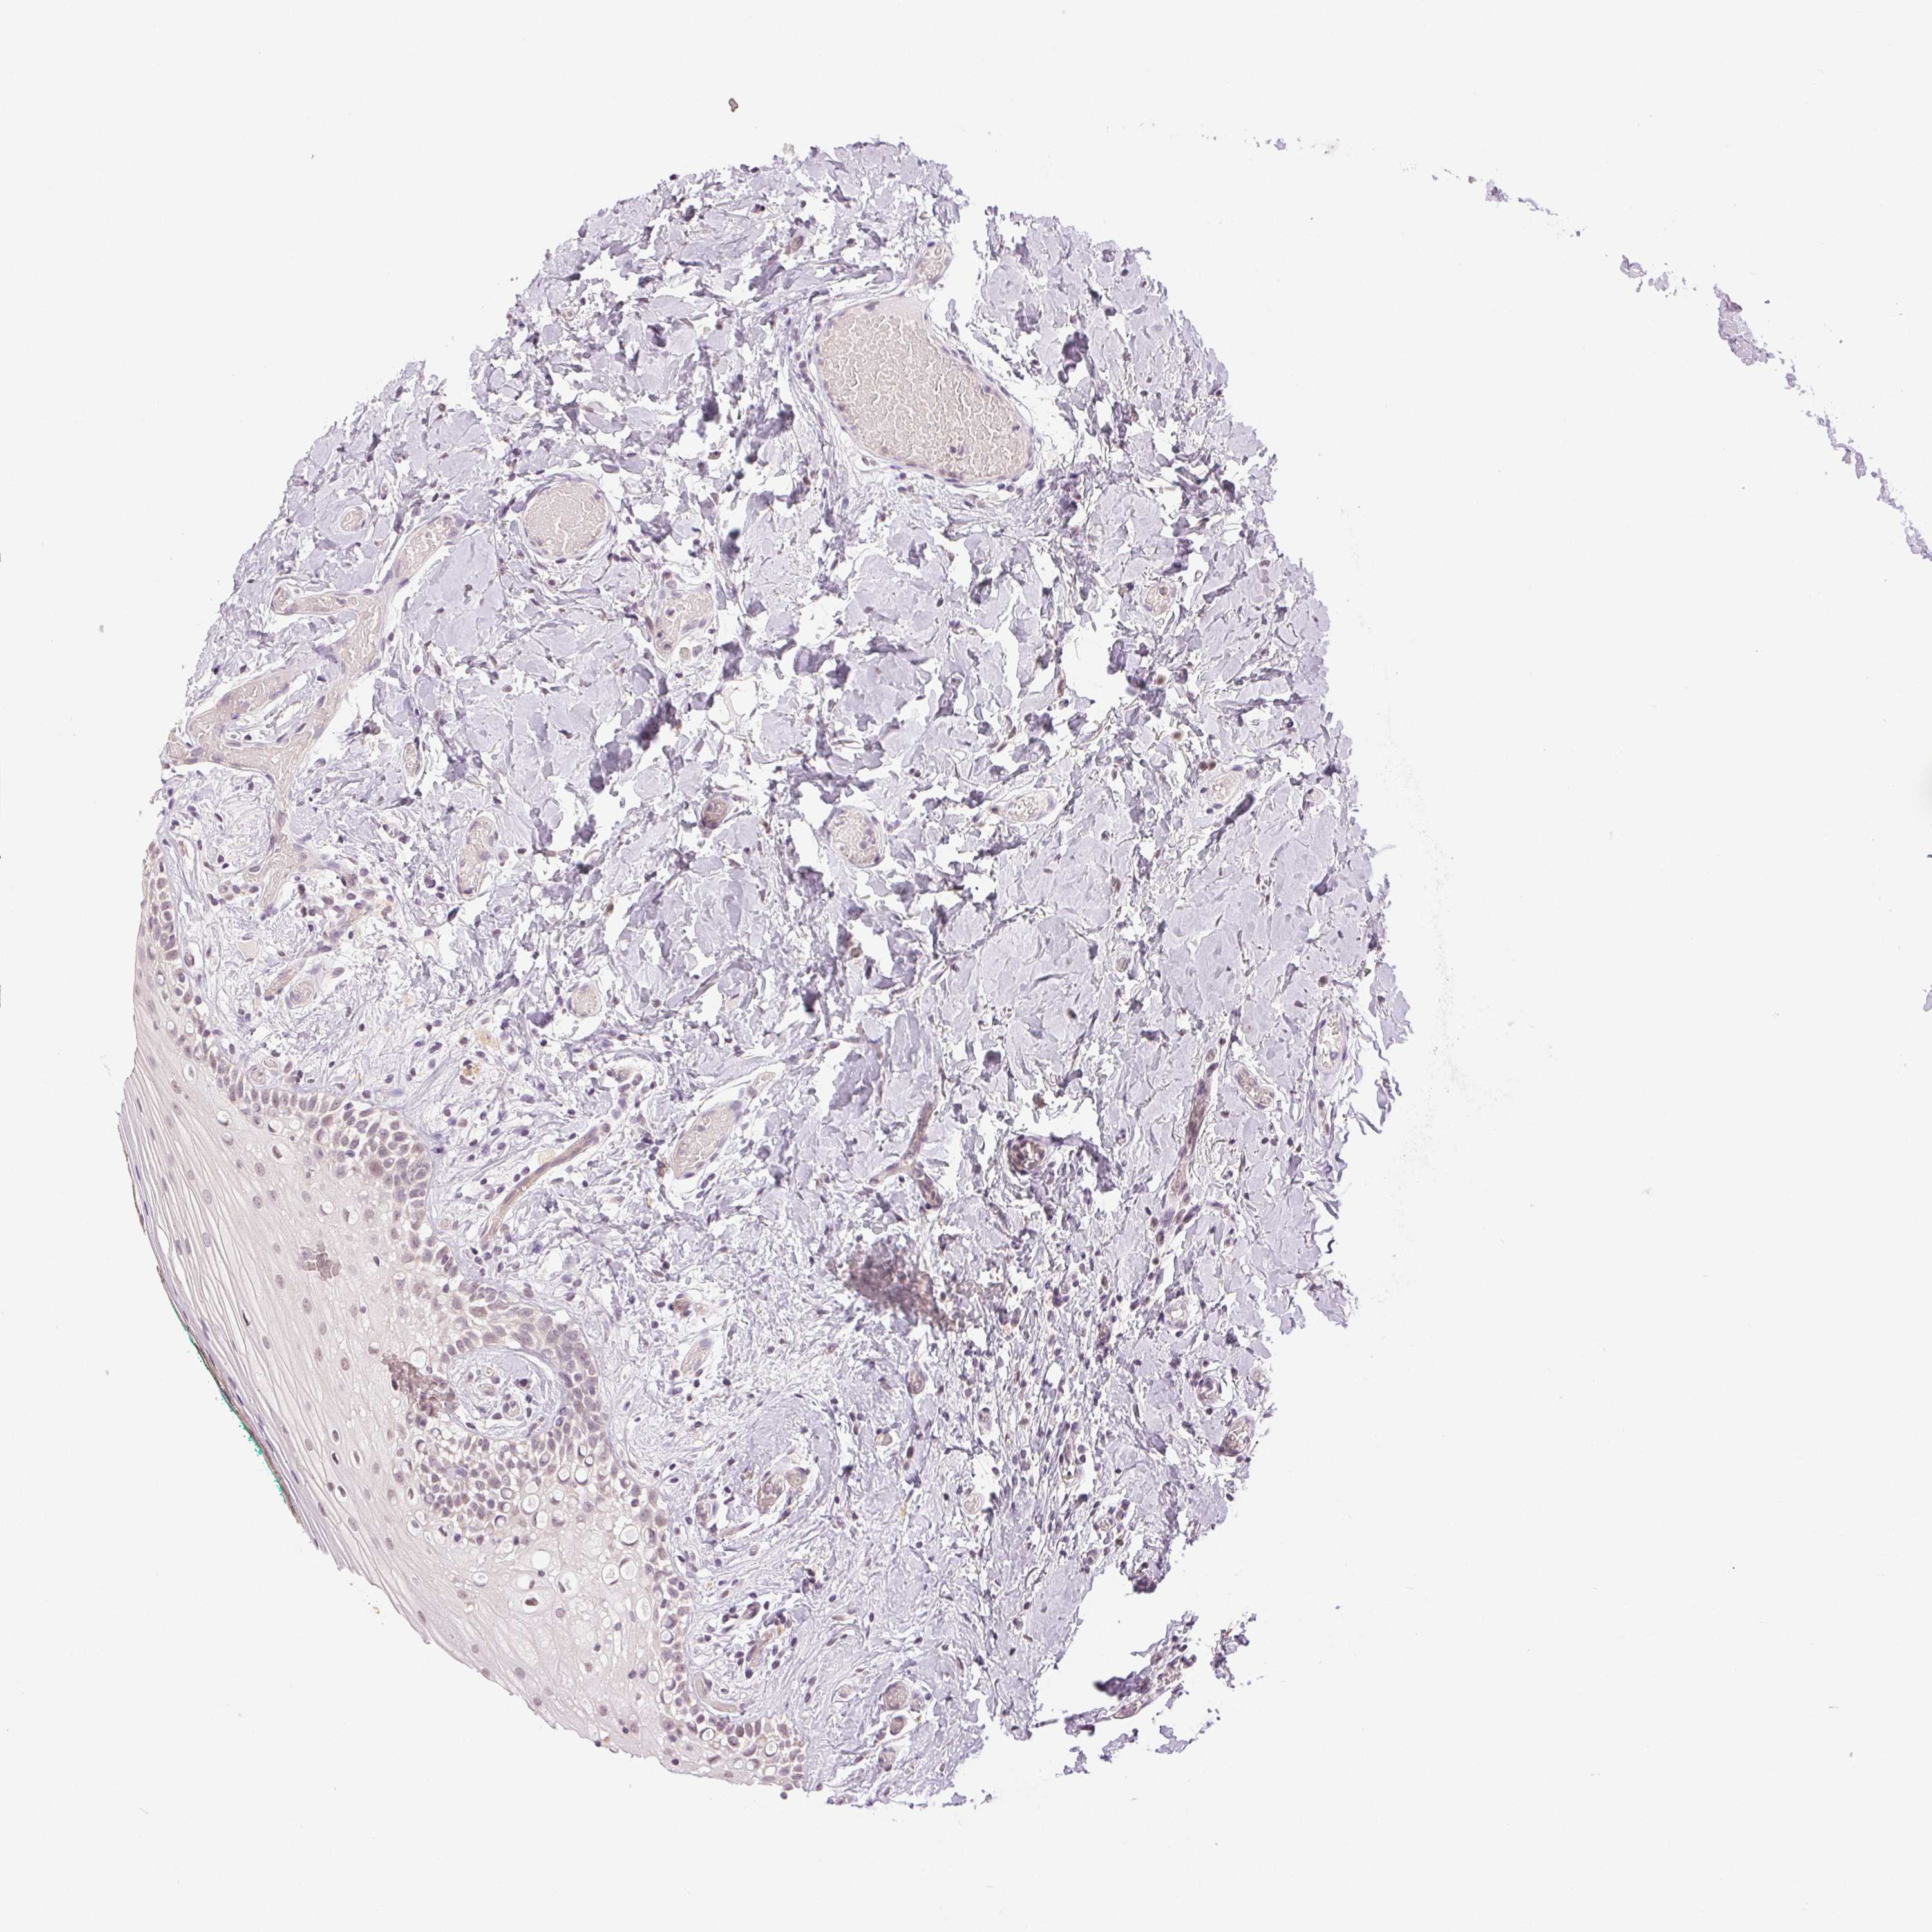

PLCB1